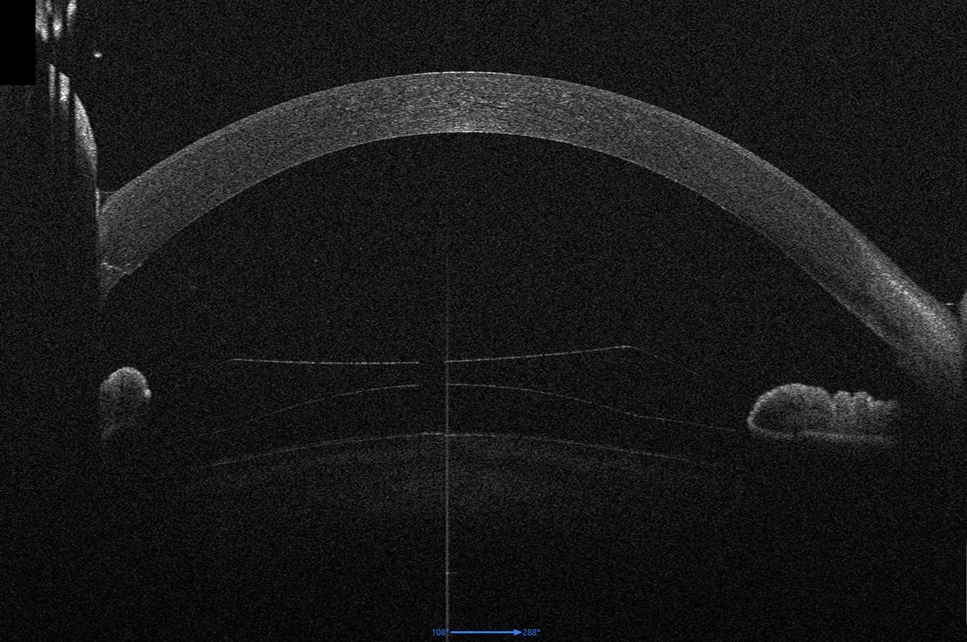

Prof. Findl operiert nach den modernsten Methoden der Hornhauttransplantation. Die meisten Operationen können unter örtlicher Betäubung und mit Kleinschnitttechnik durchgeführt werden.